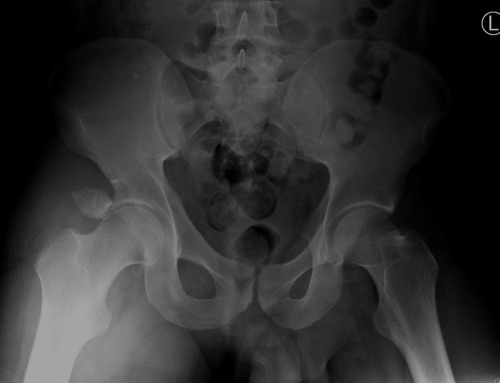

Дискуссия показывает интересные стороны развития тактики лечения переломов вертлужной впадины. Для разработки лечебной тактики сперва надо установить диагноз, и разбор показывает, что не все справляются с такой задачей! Изучение перелома надо начать из стандартных снимков: для переломов костей таза: прямой, inlet и outlet, а для перелома вертлужной впадины - снимки по Judet.

В последнее время, из-за красоты участился показ 3D снимков, хотя надо начать c обычных, и, по необходимости, компьютерная томография с 3D! Без головки бедра 3D покажет общую картину и вовлечение сустава, а более детально только в срезах КТ.

Данная картина показывает очень редкий перелом передней колонны, но перед операцией еще раз надо просмотреть обещанные дополнительные КТ срезы.

Представленные слайды Александром из Севастополя, имеет ценность, но, кроме inlet, остальные стандартные Judet рентген снимки должны показать правоту принятого решения. Возможно, здесь фиксация перелома вертлужной впадины, но по рентгену трудно понять!

Фиксация переломов передней колонны намного легче, чем остальных переломов вертлужной впадины. Любой доступ: Smith Petersen, Stoppa или ilio-inguinal. Как фиксировать перелом зависит от желания врача, можно пустить пластину по pelvic brim (linea terminalis) или более щадящее из верхнего окна пластиной, а переднюю колонну длинными межколонными винтами.

Здесь пример перелома передней стенки, где сохранен принцип фиксации передней колонны. Для доступа Smith Petersen с остеотомией ASIS. Мышца сарториус отодвинута, и сделана ре-фиксация на свое место винтами. При хорошем обзоре, наличие Farabeuf или Jungblud forceps облегчит репозицию.